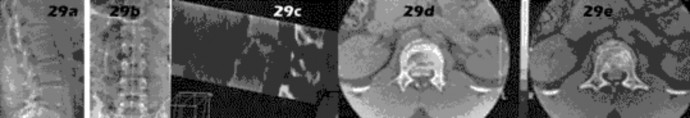

A 25-yo man sustains the injury shown in Figures 29a and 29b as a result of high-speed trauma. Examination reveals diffuse weakness in the lower extremities that is slightly worse on the right side, and decreased rectal tone and sensation. A CT scan is shown in figures 29c and 29d. Definitive treatment of the injury to the spine is delayed because of a severe pulmonary contusion. At 15 days after the injury, the patient’s neurological status remains unchanged. Management should now consist of